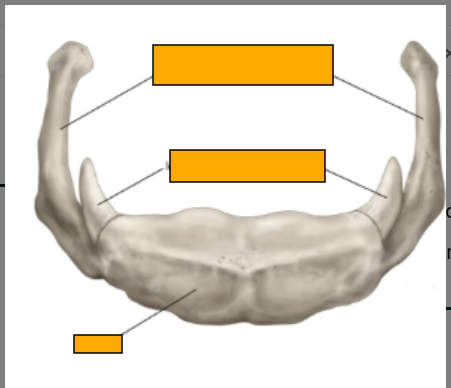

Which bone is this, label clockwise

hyoid bone

-greater horn/ greater cornu

-lesser horn/ lesser cornu

-body

Features of the hyoid bone

-no bony articulations

-stabilised by ligaments and muscles

-suspends the larynx

-supports the floor of the mouth